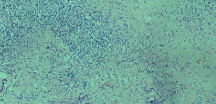

Leishmaniasis background and histology presentation. The World Health Organization (WHO) has selected cutaneous leishmaniasis as a neglected tropical disease (NTD) with growing, uncontrolled, and ignored infection affecting millions of people every year [14, 9]. It is unfortunately one of the world’s most neglected poverty-related diseases, affecting the poorest people in developing countries and it is associated with risk factors like malnutrition, immune system deficiency, migration, inadequate education, illiteracy, gender inequality, and a shortage of services [1]. Furthermore, only eight countries in the world contribute to 90% of leishmaniasis cases: Afghanistan, Algeria, Brazil, Iran, Pakistan, Peru, Saudi Arabia, and Syria [12]. It is a vector-borne infection caused by the protozoan parasite Leishmania. The vector is the female sand-fly. The lesions of cutaneous leishmaniasis vary in presentation ranging from a single self-limited skin lesion to multiple large destructive and ulcerated lesions on mostly the exposed parts of the body such as face, forearms, and lower legs [2]. Skin biopsy is considered the gold standard method for confirmation of diagnosis. The presence of large epitheloid granulomas and small hematoxylinophilic LD bodies (that are round, uniform in appearance, intracytoplasmic and sometimes distributed around the outer rim of the vacuoles) is critical for diagnosis and confirmation of leishmaniasis [4]. Large granulomas are visible at 10X but the smaller hematoxylinophilic bodies (around 3-4mm in size) are usually visible at 40X and can easily be missed if they are few in number, leading to misdiagnosis. Specialized dermatopathologists are the only ones who can diagnose these accurately based on patient history, clinical features, and laboratory diagnosis. It is thus critical to share the digitized slides of these cases from rural poor remote areas with dermatopathologists (mostly residing in urban centers) for quick diagnosis and accurate management of the patient.

We demonstrate our WSI creation workflow on Leishmaniasis cases, as shown in Figures 1 and 4. An expert pathologist reviewed the cases and annotated granulomas as well as LD bodies on the stitched images and our generated images in Figure 4. To show generalizability of our approach, we also show results on core biopsies of breast, duodenum, stomach, liver, and lymph nodes (Figure 5).